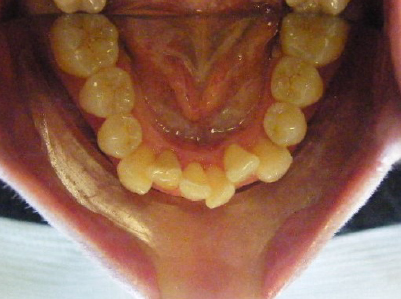

Patient 1: Severe upper and lower crowding with congenitally missing two lower adult teeth and a crossbite.